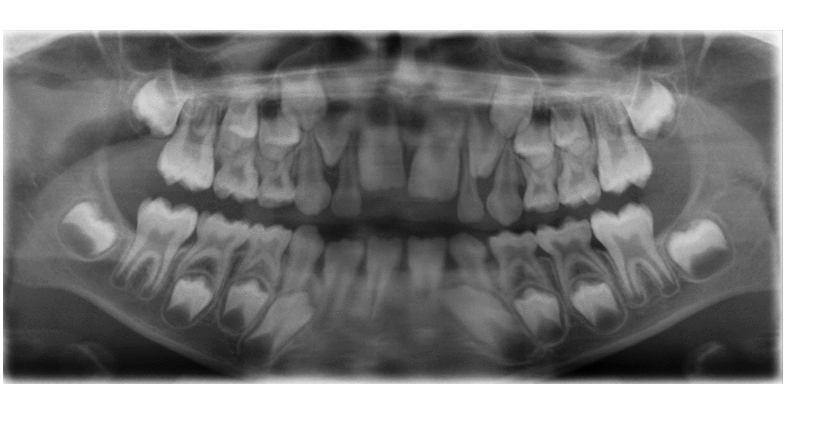

”Glad bild”

- Lutar huvudet framåt – sänker hakan. Bilden blir ”glad”.

- Underkäksincisiverna hamnar utanför det skarpa skiktet.

- Tungbenet tecknar sig över mandibeln.

- Käkledhuvudet kan hamna utanför bilden